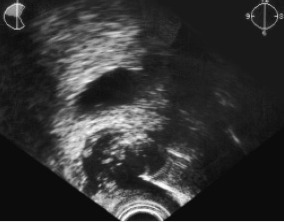

Иглы симптом — рентгенологическое проявление инфравезикальной обструкции, наблюдаемое на восходящей уретроцистограмме при доброкачественной гиперплазии предстательной железы, контрактуре шейки мочевого пузыря и склерозе простаты. Обычно симптом «иглы» на уретроцистограмме при аденоме простаты сочетается с симптомом «холма» или «берета». Симптому «иглы» аналогичен симптом «пламени свечи».